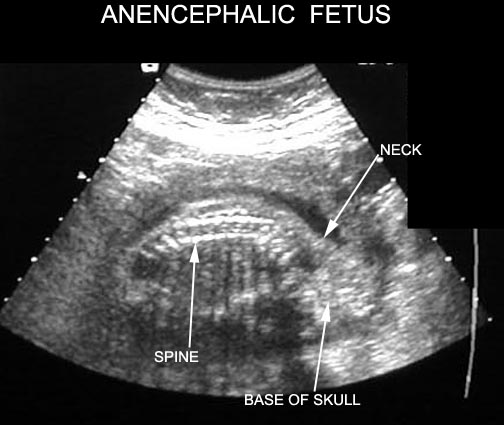

Images demonstrate a large fetus as well as a much smaller second gestation without cardiac activity. How is anencephaly diagnosed with ultrasound? A. Diagnosed in the second trimester as an absence of the telencephalon and cranial vault ... View This Document

Fetal Acrania - Prenatal Sonographic Diagnosis and Ultrasound screening for anencephaly at 10-14 weeks of gestation. CT SCAN of the aborted fetal face and base of the skull .All images are selected from bone window settings. ... Fetch Full Source